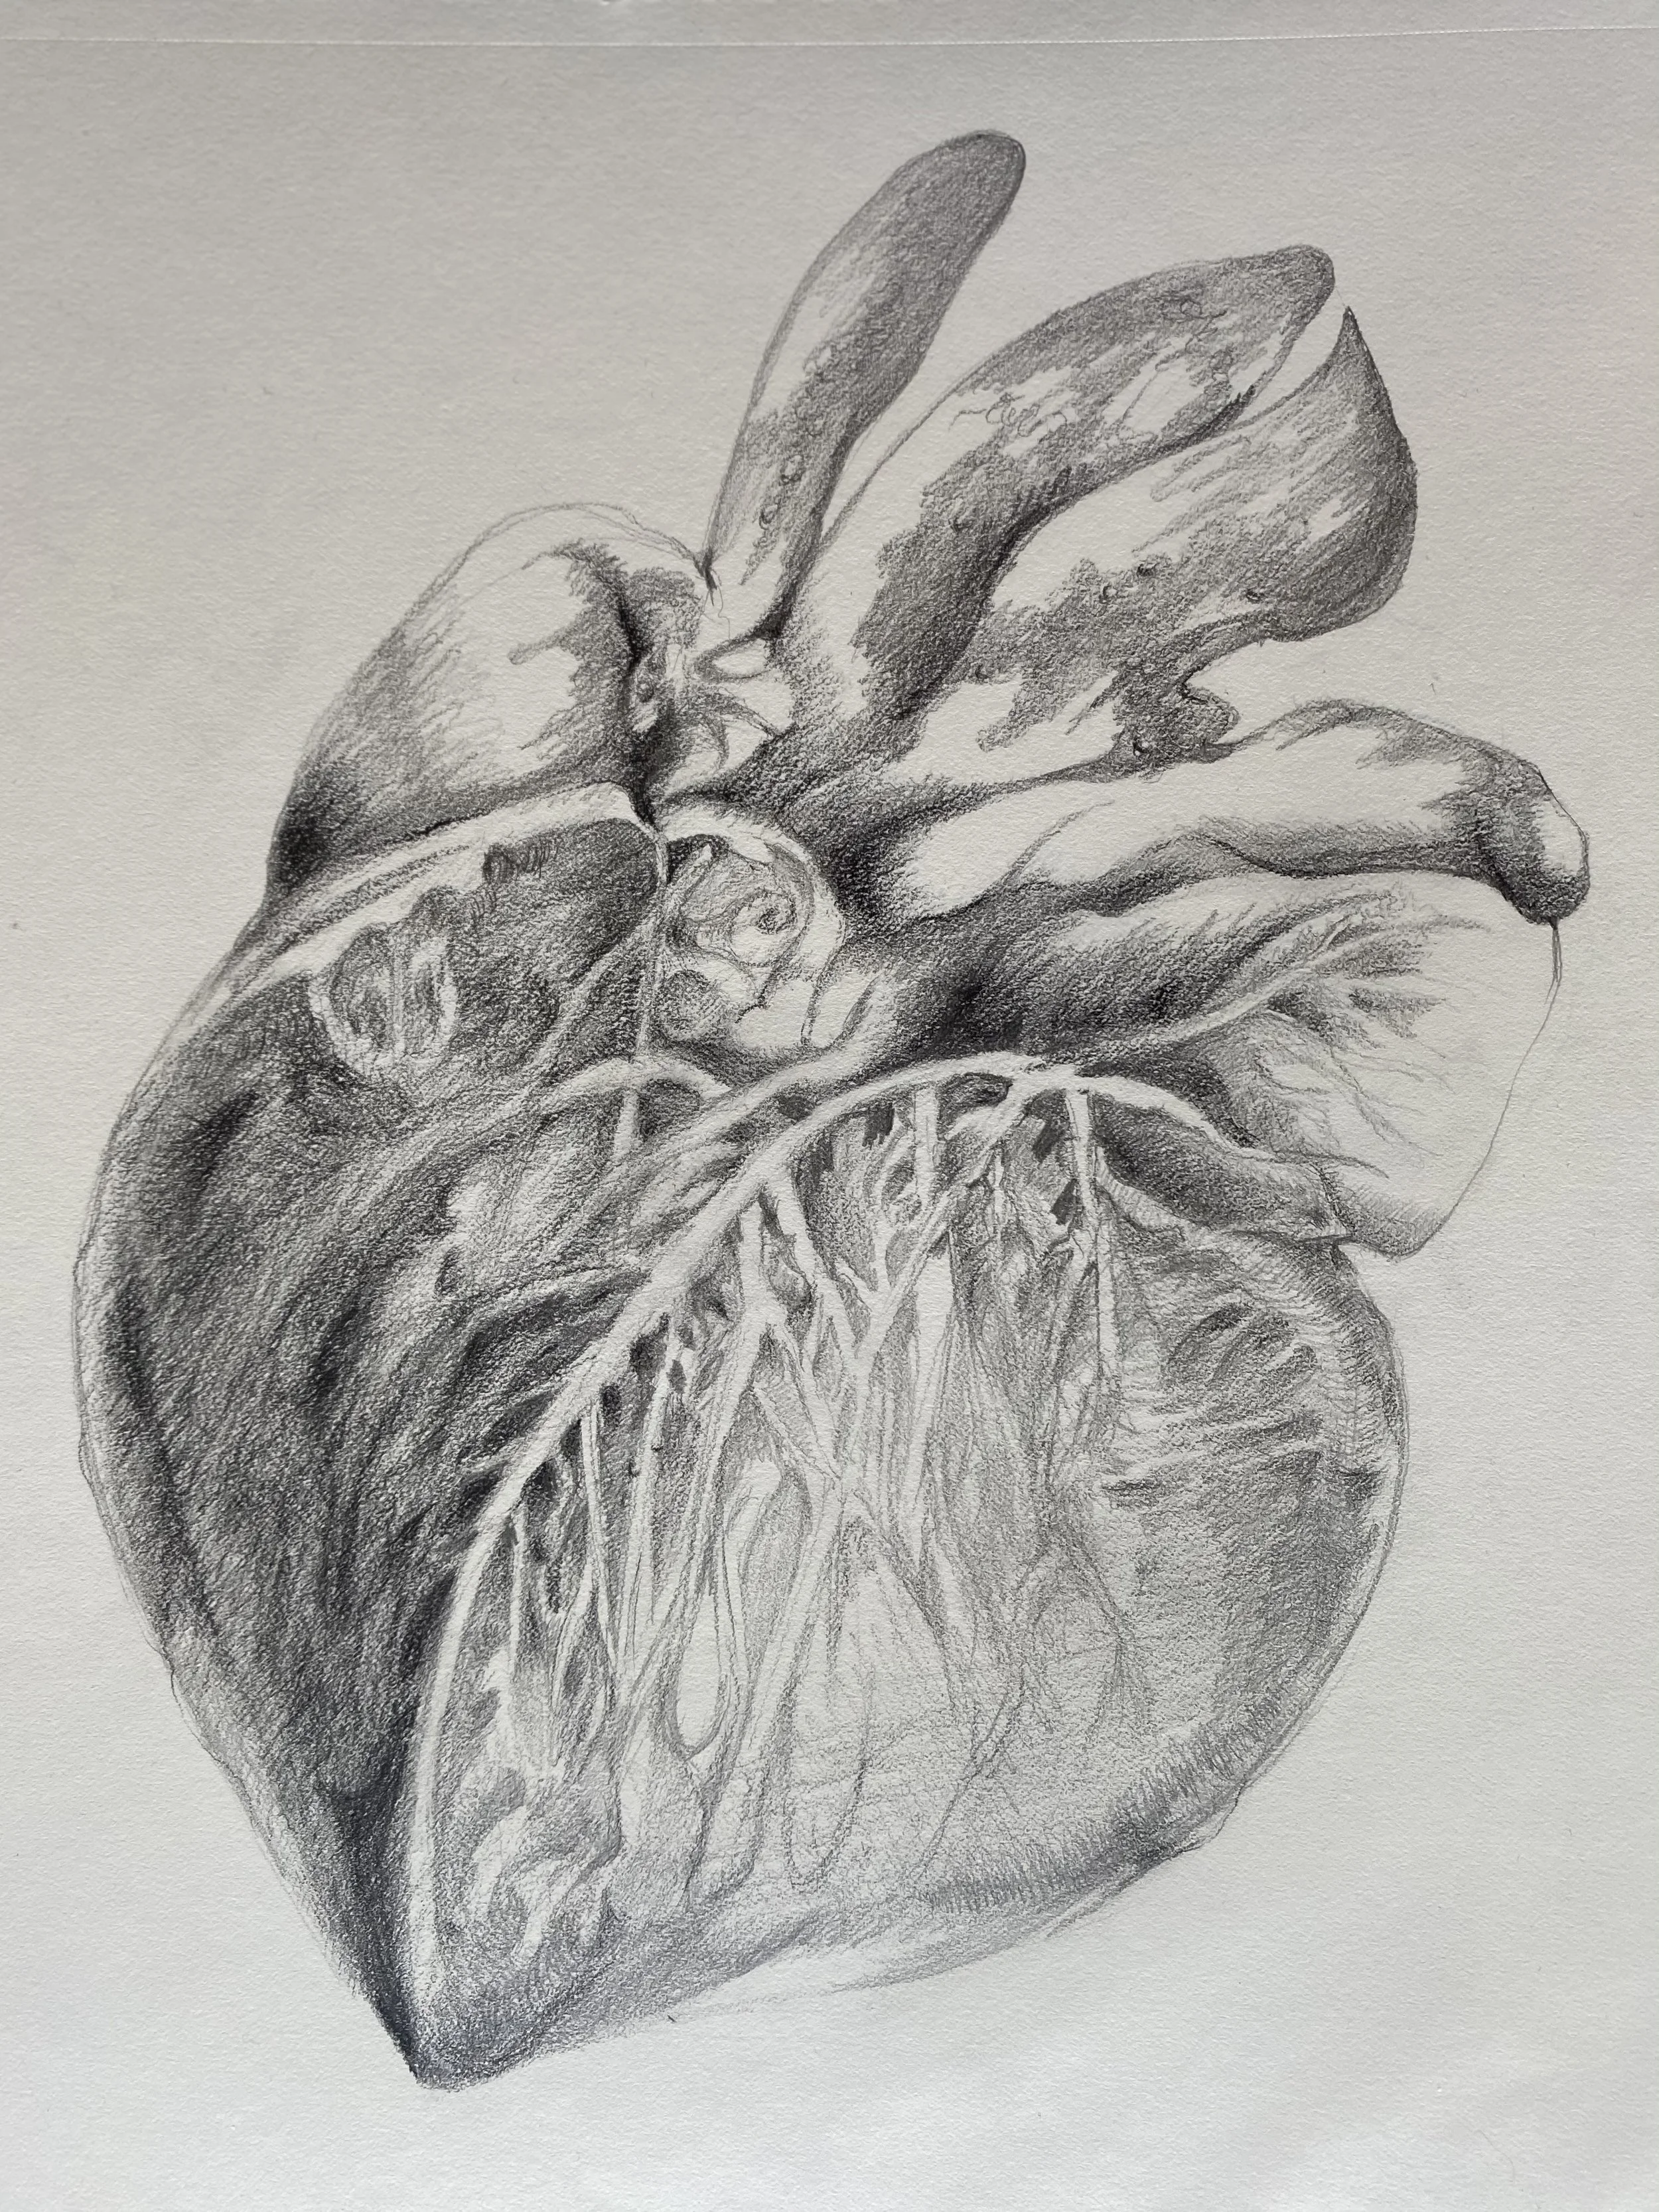

一葉心經 ( a piece of heart sutra)

Scheming Heart (心機圖)

Cardiomegaly(心肌肥大)

Heartstrigs (心弦相扣)